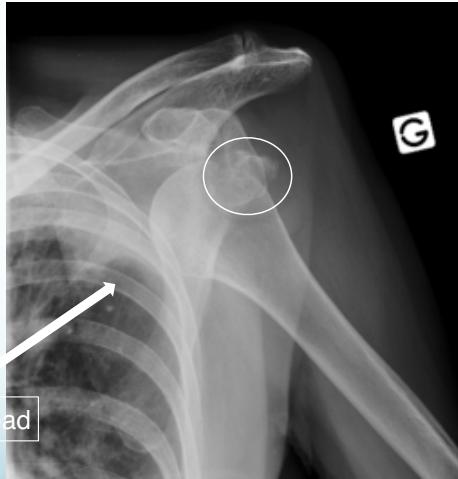

Posterior Shoulder Dislocation

Definition: The humeral head lies behind the glenoid

X-ray Findings:

- AP view:

- The humeral head is medially rotated → “Electric light bulb” sign

- The empty glenoid sign

- Posterior displacement

- Axillary & Scapular views are essential

- Rule-out fractures: neck, lesser tuberosity, glenoid